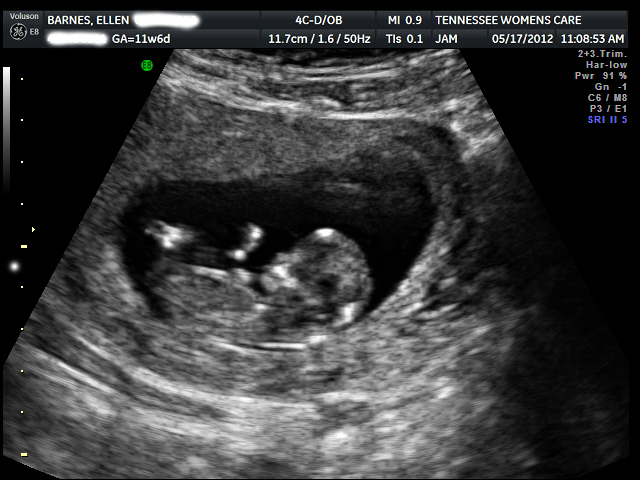

We had an ultrasound this morning and saw the baby kicking around and heard that very reassuring heartbeat. During a doctor's appointment on Monday he hadn't been able to pick up a heartbeat, and I was worried sick.

Today I feel the happiest I have in months.